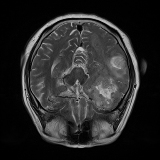

We obtain a subject-wise mean Dice score of 32.94% without any post-processing. By using a simple post-processing with erosion and dilation with filters, this number improves to 48.20% mean Dice score. In comparison, a similar study conducted by [3] consisting of a multitude of algorithms including AnoVAEGAN [4] and f-AnoGANS, obtained a best mean score of 27.8% Dice after post-processing by f-AnoGANS. Before post-processing the best method was Constrained AutoEncoder [8] with a score of 9.7% Dice. An exhaustive list is presented in Table 1. Figure 4 shows sample images of our results.

We obtain a subject-wise mean Dice score of 63.67% for the brain tumor segmentation. Utilizing a simple post-processing scheme of erosion and dilation with filter, we improve our mean Dice score to 68.01%. Figure 4 shows samples generated by our ASC-Net and Table 2 shows our before and after post-processing results. We attempted to apply f-AnoGANs [34] by following their online instructions and failed to generate good reconstructions as shown in Figure 5. The failure of AnoGANs in the reconstruction brings to light the issue with the regeneration based methods and the complexity and stability of GAN-based image reconstruction.

We obtain a slice-wise mean Dice score of 32.24% for this liver lesion segmentation, which improves to 50.23% by using a simple post processing scheme of erosion and dilation with filter. Sampled results are shown in Fig. 4. Compared with [42], which obtains a mean Dice score of 40.78% and a standard deviation of 0.43%, we improve the mean Dice score by almost 10%, but has a much larger standard deviation. Unlike [42], where the network is pre-trained on a artificial tumor dataset, and hence the pipeline customized for tumor segmentation, our method do not need such information beforehand. We notice that our standard deviation for BraTS dataset is similar to [27]. This is because novelty/anomaly detection algorithms without a pre-defined task would suffer from the co-morbidities issues discussed in Section 5.